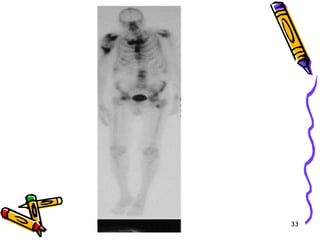

Technetium bone scansTechnetium bone scans are indicated to detect skeletal metastases and to determine the presence of multiple lesions in such entities as osteochondroma, enchondroma, fibrous dysplasia, and histiocytosis. Bone scans frequently are falsely negative in multiple myeloma.32

33

With the exception of myeloma, however, virtually all malignant neoplasms of bone demonstrate increased uptake on technetium bone scans34

. A normal bone scan is therefore very reassuring; however, the converse statement is not true because most benign lesions of bone also demonstrate increased uptake35